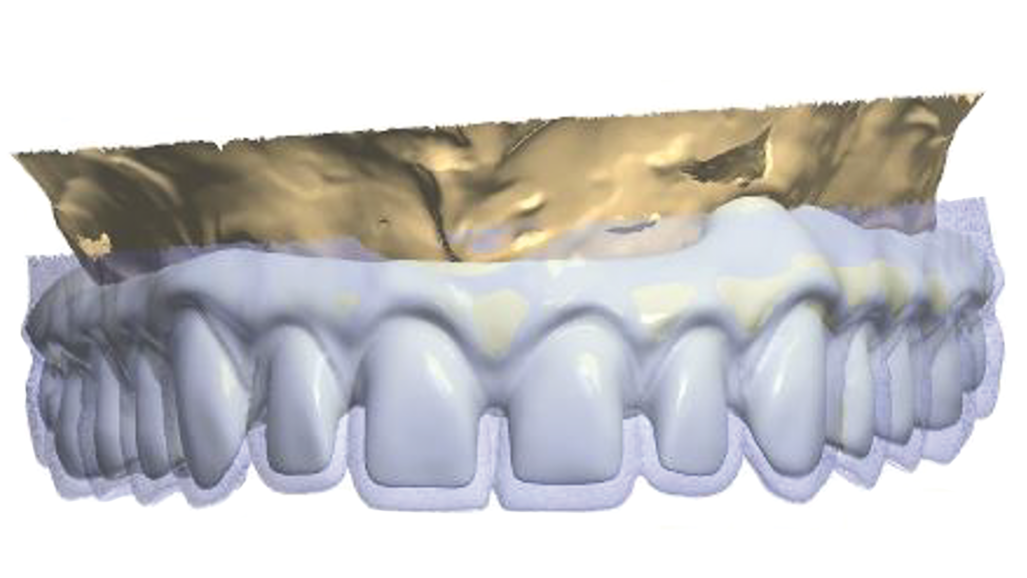

The model was scanned while the abutments were made ready in such a way that they could serve as telescopic crowns, also in the final stage (Fig. 9). Primary and secondary telescopic crowns were designed on the abutments (Figs. 10 & 11) on the assumption that secondary crowns had been made ready twice, that is, for the sake of temporary prosthesis and at the same time for gluing it into the final construction (Figs. 12 & 13). Abutments were mounted on implants by means of Pattern Resin (Figs. 14 & 15) in such a way that the position does not change during mounting.

A temporary skeletal prosthesis, based on four telescopes, shall be placed on such a foundation (Figs. 16 & 17). Primary telescopic crowns were glued last (Fig. 18).

Secondary telescopic crowns, made from acetal by means of the CAD/CAM virtual designing method, were tried on primary crowns (Fig. 19). Figures from 20 to 22 present a macroscopic view of zirconia primary crowns testing and acetal secondary crowns. At that stage, our patient received a temporary prosthesis, while lateral implants remained unloaded (Figs. 23 & 24).

In the second part of the article, we will present the designing process (Figs. 25 and 26) along with the process of manufacture of the final construction made from TRINIA material with glued zirconia crowns as well as veneering by means of pink composite material.